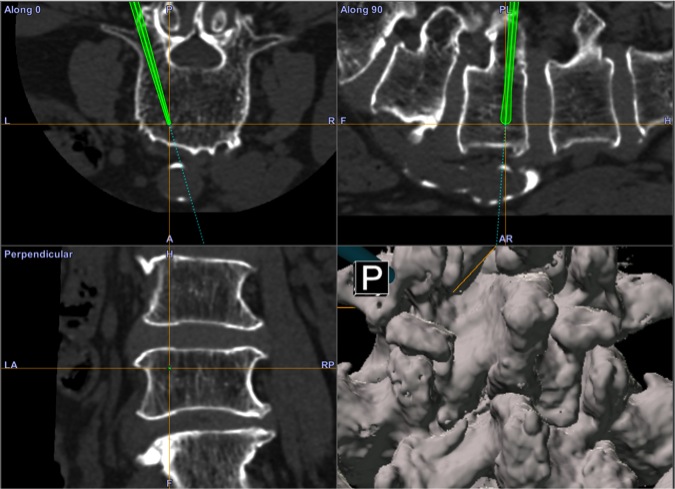

■利用三維電腦導航技術植入螺絲,即使是骨質相對疏鬆亦可用此方法進行固定。